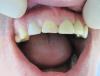

anvladd Опубликовано 21 января, 2013 Автор Поделиться Опубликовано 21 января, 2013 спустя 3 месяца Ссылка на комментарий

iБолит Опубликовано 21 января, 2013 Поделиться Опубликовано 21 января, 2013 Первый вопрос диастемой - почему ее решили закрыть? Ортодонтия или будушая работа с клыком погла ее решитьВторое -поднять прикус и делать весь верх, это помогло бы добиться лучших результатовТретье - если делали инд абатмент почему он не индивидуален? Понимаете почему светится у шейки? то место которое образовалось оно чем закрылось? десну не дотяните и будет полость, даже если цементом залили ничего хорошего. Как спасение может быть композитом попробовать ( чисто догадка) Серьезно смотрится не очень удачно когда ширина больше 11 зубаИ еще одно. проблема с цветом как никак.Из луших пожеланий говорю, а не так чтобы подстегнуть, просто очень много ошибокНо однозначно переделывать Ссылка на комментарий

anvladd Опубликовано 21 января, 2013 Автор Поделиться Опубликовано 21 января, 2013 Переделывать не буду, пац доволен(пришел только с этим зубом).Про диастему честно и не думал.Весь верх делать предлагал, отказался!На счет абатмента тоже расстроился когда работа пришла, но выбора не было, пришлось ставить его. Пустота ничем не закрылась,получился нависающий край коронки.Это моя первая работа на инд абатменте и цирконе. Цель была поставить зуб и не заморачиваться на эстетике. Ссылка на комментарий